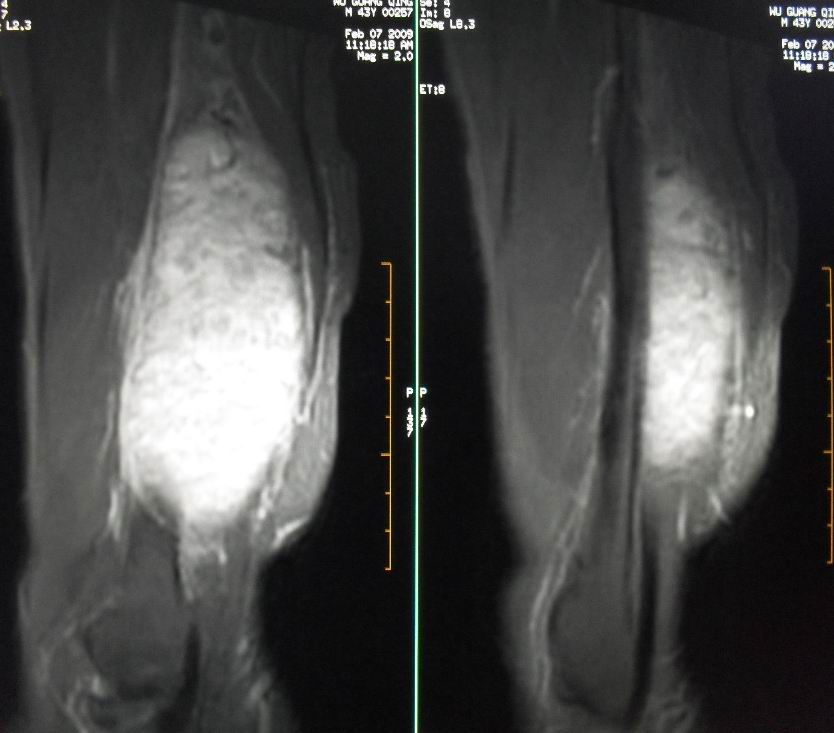

患者男43,右小腿后部软组织肿块2~3年,近期增大明显。平扫加强化。已手术。

1)呈等长t1混杂t2信号,其内见多发类圆形长t1长t2异常信号,病灶主要沿肌间隙生长,但有完整的包膜.gd_dtpa显示:病灶呈明显不均匀的强化,但未见迂曲的强化血管影.

呈等长t1混杂t2信号,其内见多发类圆形长t1长t2异常信号,病灶主要沿肌间隙生长,但有完整的包膜

本病例软组织肿块大,内信号不均匀,有多个囊变区,包膜完整,本片经山东省医学影像研究所mri室王主任会诊术前考虑良性肿瘤,不排除恶变,在北京某医院手术,穿刺及术后病理均为良性,未发现恶变。

本病例软组织肿块大,内信号不均匀,有多个囊变区,包膜完整,本片经山东省医学影像研究所mri室王主任会诊术前考虑良性肿瘤,不排除恶变,在北京某医院手术,穿刺及术后病理均为良性神经鞘瘤,未发现恶变。[face=宋体][/face]

谢谢楼主反馈手术结果!该病灶巨大,但与周围组织分界清晰,其内低密度规整,均支持良性病变。